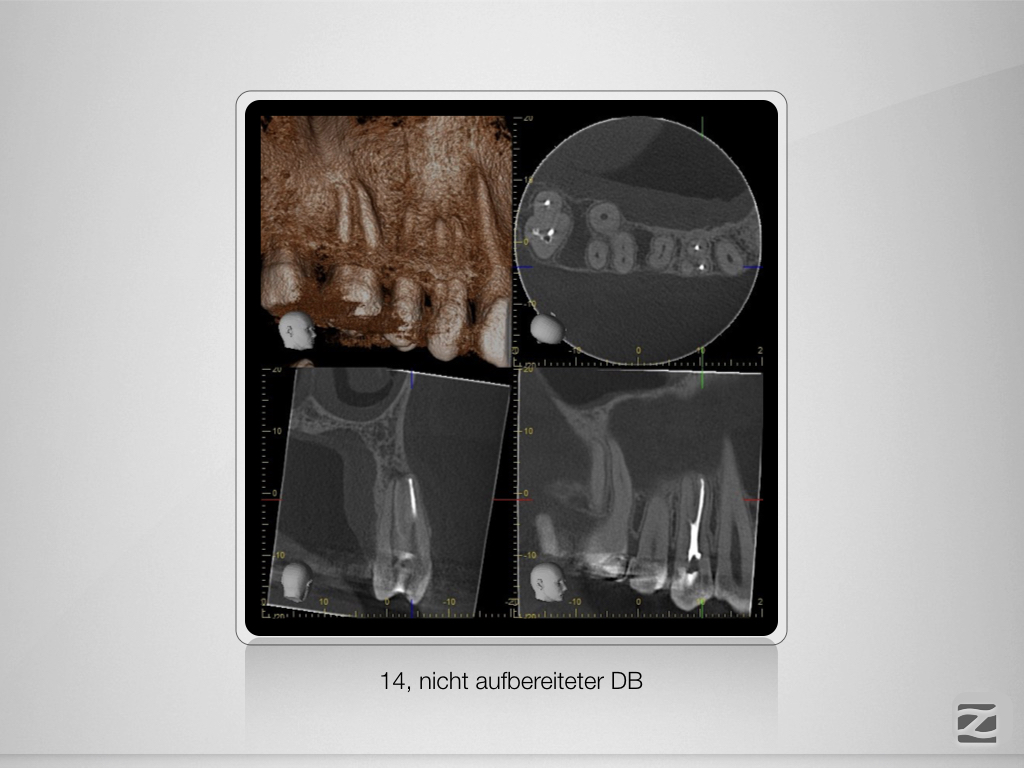

14D.004

Schöner Dreier